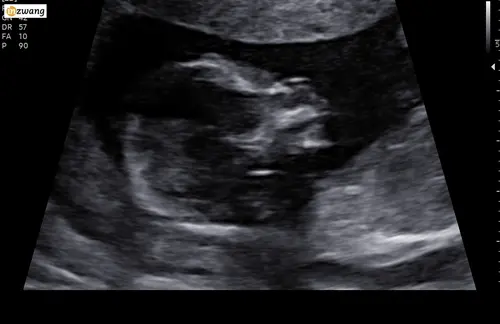

Update: Vanmorgen de echo gehad in LUMC. We kregen daar de bevestiging dat het kindje inderdaad een teruggetrokken/kleine onderkaak heeft. Verder is het kindje nog helemaal nagekeken en en waren wederom geen andere afwijkingen te zien. Na de echo hadden we een gesprek met de gynaecoloog en die vertelde ons eigenlijk 3 scenario's: -Het is gewoon erfelijk en valt binnen normaal, ze heeft gewoon een kleinere onderkaak zonder verdere aandoening

Mijn dochter had ook een klein kinnetje met de 13 weken echo. Ik ben doorverwezen naar het Isala ziekenhuis, hier ben ik twee keer geweest voor extra controle.

Ze hebben bij mijn dochter gemeten hoever de kin terug stond in vergelijking met haar bovenlip (geloof ik? tijdje terug alweer 🙈). Dit mocht een bepaalde aantal graden afwijken, maar hier zat ze ver overheen. Nog een keer terug geweest met 20 weken, en toen was het weer 'normaal'. Ik had de optie voor een vruchtwaterpunctie, maar heb zelf gekozen om dit niet te doen aangezien er niks uit de NIPt test was gekomen.

Vandaag hadden we de 20 weken echo in Leiden. Alles was verder goed, maar de kaak is nog steeds teruggetrokken.

Hierover krijgen we als goed is maandagmiddag een terugkoppeling. Er word onder andere besproken of een bevalling in een gespecialiseerd ziekenhuis noodzakelijk is en de kinderarts kan aan de hand van echo's die nog gaan volgen in de zwangerschap beter bepalen hoe erg de kaak teruggetrokken is en of dit problemen kan veroorzaken bij het ademen na de geboorte. Ook zal de groei van de baby in de gaten gehouden worden gedurende de weken tot de bevalling.